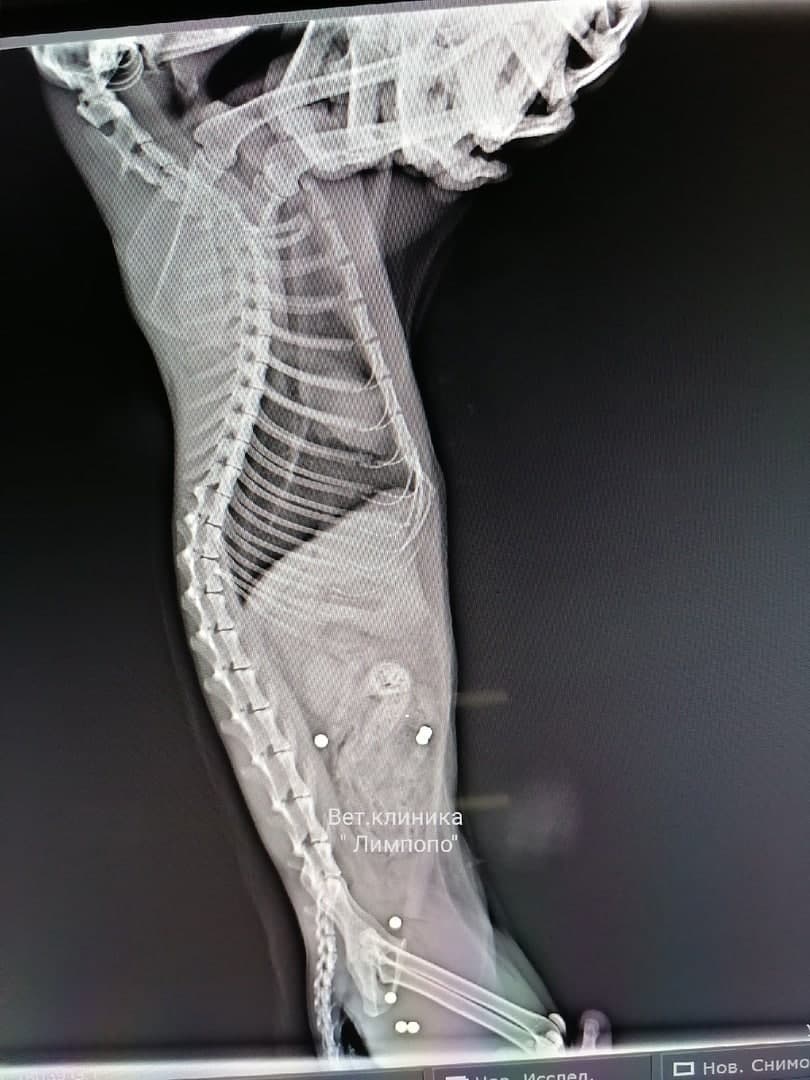

Полиция начала проверку после попадания в красноярскую ветклинику кошки с семью пулевыми ранениями

Как рассказали сотрудники клиники «Липмопо», 7 пулевых ранений у животного выявились на рентгене. После ранения кошка выжила, но сильно пострадала.

Полицейские предполагают, что в кошку стреляли из пневматики. В самой клинике произошедшее пока не комментируют.